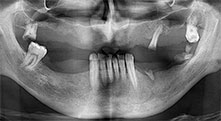

For what indications do you use the saws?

Bratu: We routinely use the instruments for harvesting bone blocks and splitting alveolar ridges. We also use the Piezomed B6/B7 for osteotomy of impacted teeth and removing failed implants. All indications that require deep, clean cuts.